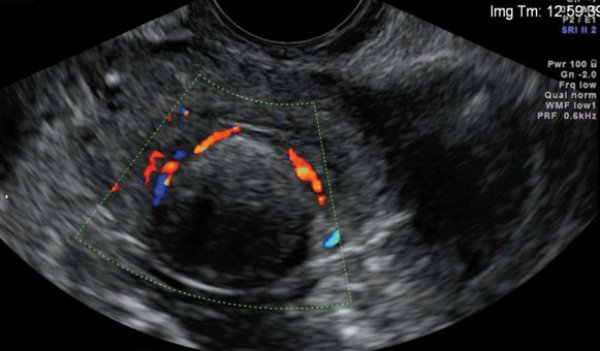

De hecho, la medicina tradicional puede ayudar incluso en las formas graves de la enfermedad. Se trata de un remedio basado en aloe y miel, del que la mujer tomó una cucharada tres veces al día, durante un mes. ¡Cuál fue la sorpresa de su médico cuando el ultrasonido no reveló ningún tumor!